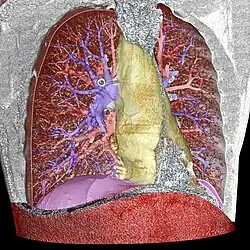

Volume segmentation

- blue: pulmonary arteries

- red: pulmonary veins (and also the abdominal wall)

- yellow: the mediastinum

- violet: the diaphragm

Image segmentation is a manual or automatic procedure that can be used to section out large portions of the volume that one considers uninteresting before rendering, the amount of calculations that have to be made by ray casting or texture blending can be significantly reduced. This reduction can be as much as from O(n) to O(log n) for n sequentially indexed voxels. Volume segmentation also has significant performance benefits for other ray tracing algorithms. Volume segmentation can subsequently be used to highlight or expose[14] structures of interest.